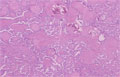

- ★(8)Papillary carcinoma of the thyroid

Macroscopic findings. Irregular, whitish, nodules (arrows) of papillary carcinoma on the cut surface. Benign nodules (dotted line) of nodular goiter also are detected in the thyroid.